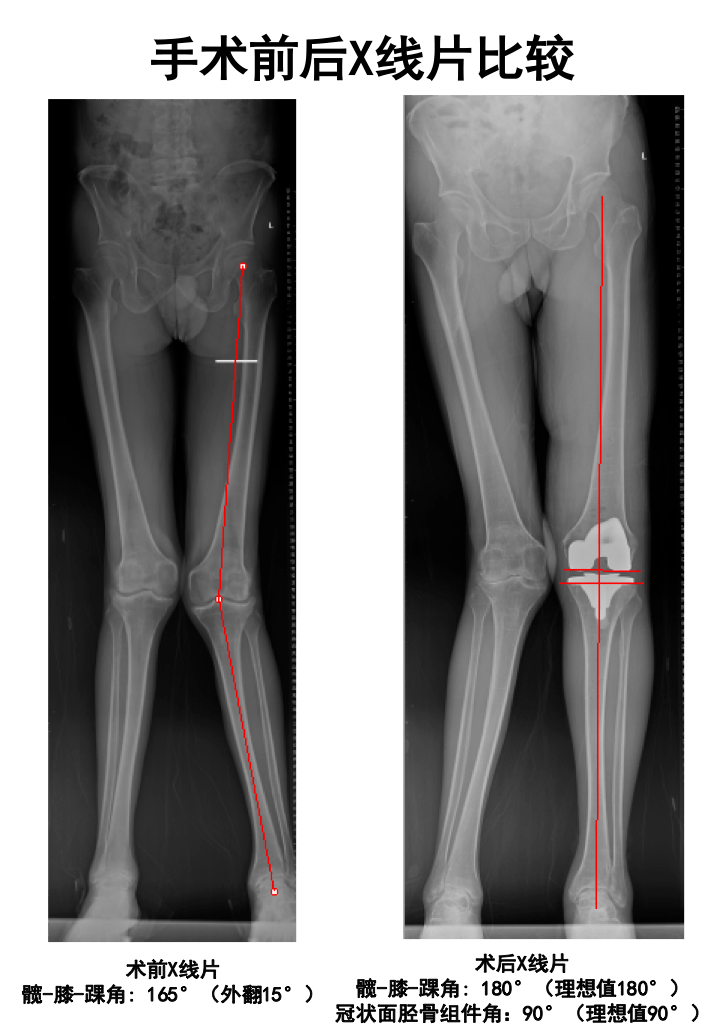

膝骨关节病合并膝外翻畸形,九江市中医医院为其成功实施全膝关节置换术